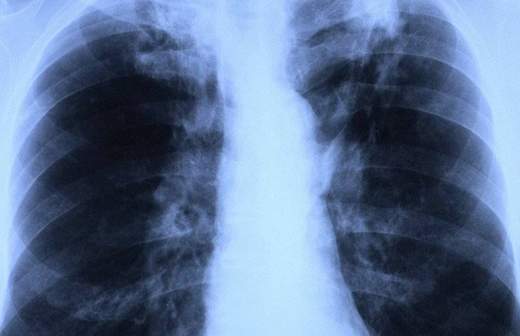

Минздрав намерен победить туберкулез в России к 2030 году

Минздрав планирует ликвидировать туберкулез в России к 2030 году, заявила глава ведомства Вероника Скворцова.

«Мы начинаем серьезнейший цикл политических многосекторальных преобразований в области туберкулеза с единственной целью — ликвидировать эту болезнь к 2030 году», — сказала министр в ходе выступления на Всероссийской научно-практической конференции «Междисциплинарный подход в решении проблем туберкулеза».

Скворцова добавила, что смертность от туберкулеза в России с каждым годом снижается на 15–17%.